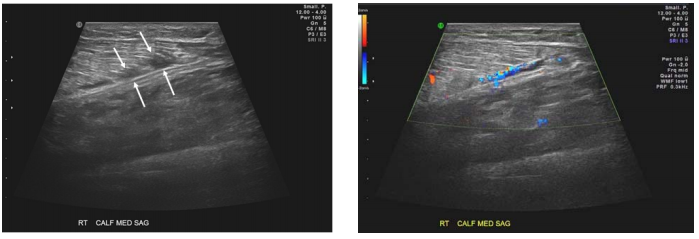

73 一位 49 歲男性病人,於網球比賽中摔倒之後,右小腿腹腫脹疼痛 3 天。下圖為灰階及彩色杜卜勒超 音波針對小腿腹內側縱向掃描,箭號處最可能的診斷為何?

(A)腓腸肌部分撕裂(partial tear of gastrocnemius) (B)腓腸肌血管瘤(hemangioma of gastrocnemius) (C)小腿膿瘍(lower leg abscess) (D)阿基里斯肌腱斷裂(Achilles tendon tear)